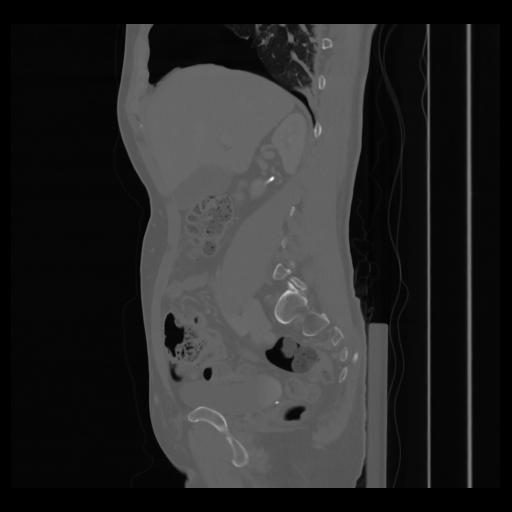

36 CUERPO,CE,Sagittal,3.000,CUERPO,Sagittal,